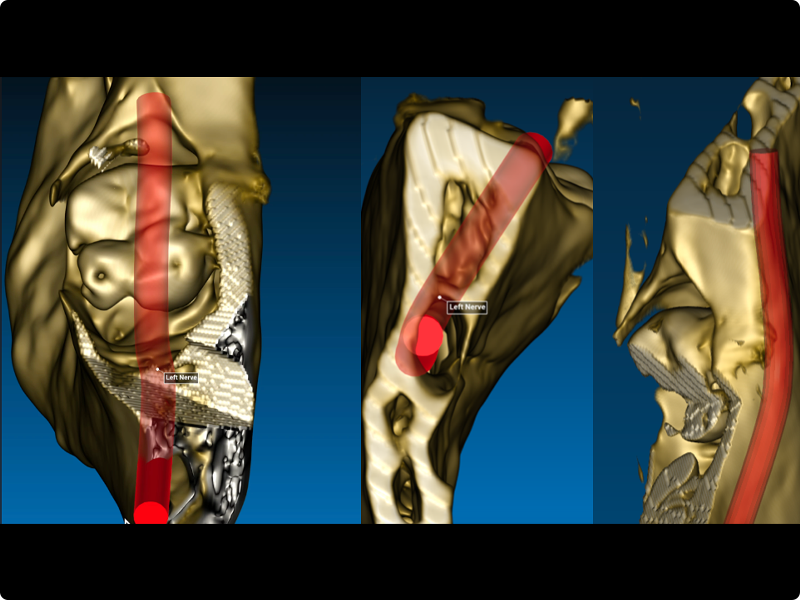

- Radiological, clinical and anatomical evaluation.

- Clinical and radiological evaluation.

- Osteotomy.

Clinical cases of impacted third molar surgery and explanatory videos